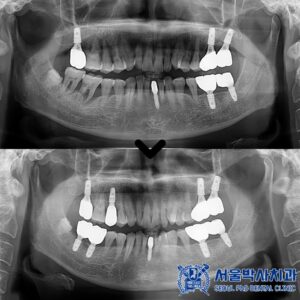

성남치과 남편 소개로 왔어요. 골다공증 환자분 뼈이식을 포함한 어금니 무절개 임플란트 사례

성남치과 남편 소개로 왔어요. 골다공증 환자분 뼈이식을 포함한 어금니 무절개 임플란트 사례 안녕하세요. 성남치과 서울박사치과입니다. 골다공증은 뼈의 밀도가 감소하고 뼈가 약해지는 질환으로, 주로 노년층에서 발생합니다. 이로 인해…